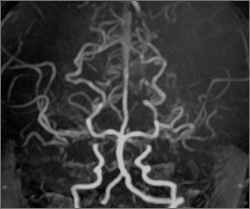

4歳女児症例 脳MRA検査

両側STAMCAバイパス術後